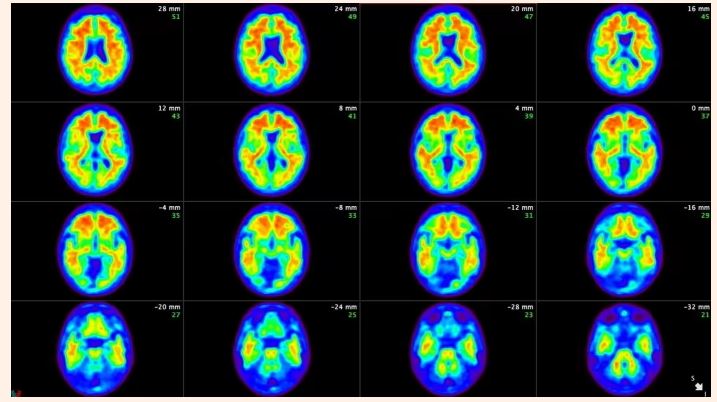

阿兹海默症是一种脑部疾病,也是最常见的失智症类型。

据英媒报道,专家们正在改善医生诊断这种发展性脑部疾病的方法,依据患者的认知与生物学变化设计了一套7分制的评分量表。新版指引将取代2018年的版本,原因在于例如β淀粉样蛋白等与阿兹海默症有关的关键蛋白质血液检测方法进步,以及有更多新疗法须在治疗前先确认疾病病理。

在新的诊断方法下,患者将被按照认知变化程度以及是否检查出异常疾病生物标记物,由医师评给1到7分,加上a、b、c、d等4个生物阶段,例如,第1a阶段代表患者完全没有症状,但生物标记异常。

第2期患者可能出现异常生物标记与非常细微的认知或行为变化。第3期则大致相当于轻度认知障碍,即症状前的阶段。而第4、5、6期则等于轻度、中度与重度失智。新的诊断量表还包含第0期,是针对那些带有罹患阿兹海默症基因的族群所设,例如唐氏症患者,因为唐氏症患者中有75%会在成年后罹患阿兹海默。